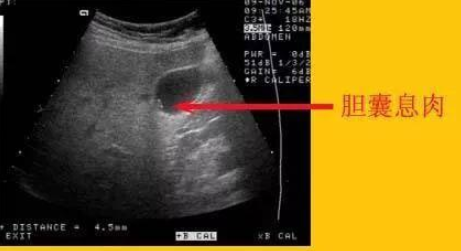

胆囊上长息肉是否要紧取决于多个因素息肉大小如果息肉小于1cm,且患者没有任何症状,通常可以先观察,定期随访每半年到一年进行一次肝胆彩超检查,用于评估胆囊息肉的大小和增长速度症状表现如果胆囊息肉引起反复的右上腹闷痛胀痛或绞痛等急性胆囊炎的症状,或者合并胆囊壁明显增厚充血水肿,以及。

胆囊有息肉是比较严重的情况,需要引起足够重视胆囊息肉样病变不是一个单一的疾病,主要分为以下几种类型,其严重性和处理方式也各不相同癌性病变特点胆囊黏膜层有局限性的隆起性病变,且短期内发展相对较快处理方式需要及时进行胆囊切除术,如果手术及时,病人生命没有大的影响,五年存活率。

胆囊多个息肉的严重程度取决于息肉的性质和大小以下是关于胆囊多个息肉的详细解答多为胆固醇性息肉胆囊内的多个息肉,临床经验上多考虑是胆固醇性息肉这种息肉一般是良性的,但具体确诊需要手术后送至病理科进行进一步检查腺瘤性胆囊息肉需警惕胆囊息肉还可能是腺瘤性的对于腺瘤性胆囊息肉,有个别。